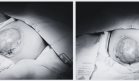

La biopsia muscular abierta proporcionó el diagnóstico definitivo, mostrando un patrón histológico característico de mionecrosis diabética. El análisis microscópico reveló variación significativa en el diámetro de las fibras musculares, fibrosis endomisial y numerosas fibras necróticas en proceso de regeneración, identificables por su basofilia y núcleos prominentes.

El estudio inmunohistoquímico demostró infiltración por macrófagos CD68+ con evidente mofagocitosis, patrón consistente con degeneración muscular activa. Estos hallazgos se correlacionaron perfectamente con el cuadro clínico, permitiendo descartar otras entidades como miopatías inflamatorias autoinmunes o amiotrofia diabética, especialmente tras la obtención de estudios serológicos negativos para autoanticuerpos específicos y una electromiografía que mostraba cambios miopáticos focales sin evidencia de neuropatía.